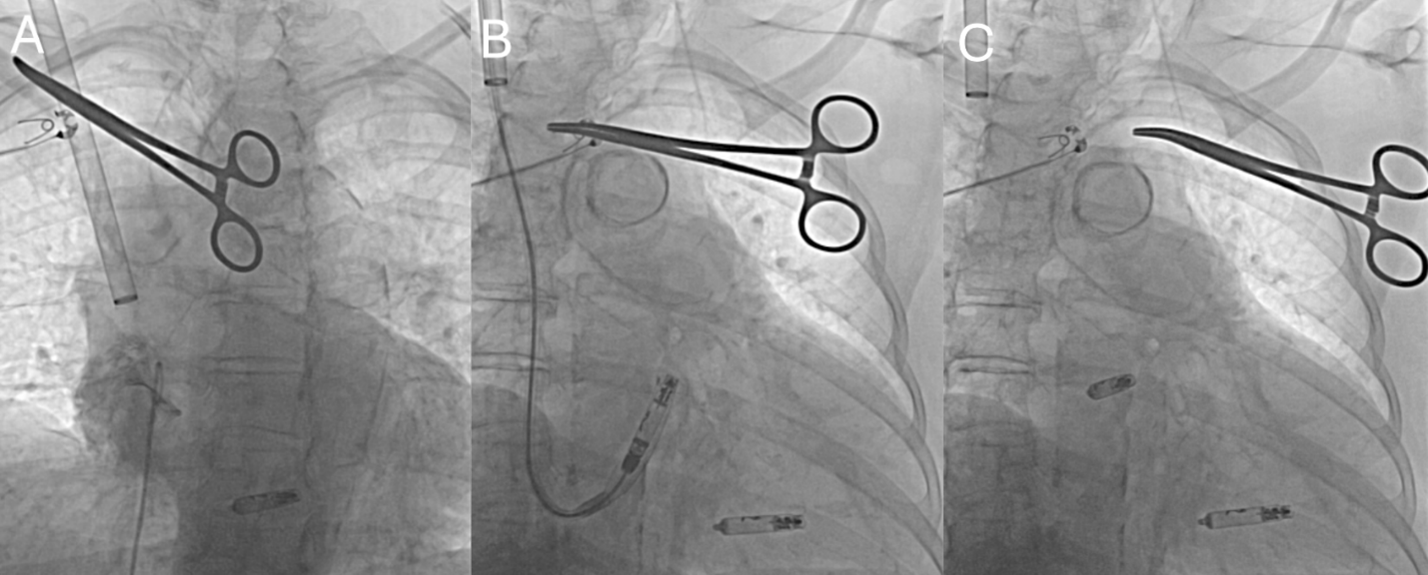

In cases of AVEIR AR, following successful placement of the VR device, an AVEIR AR was implanted via the same RIJ approach. The delivery sheath was advanced into the right atrium, and the delivery system was flexed to engage the base of the right atrial (RA) appendage. Contrast injection was used to confirm appendage depth and orientation. With fine adjustments in deflection and torque, the sheath was aligned toward the anterolateral RA wall at the appendage base, permitting secure fixation of the device. Deployment and electrical interrogation were performed using standard criteria (Figure 3).